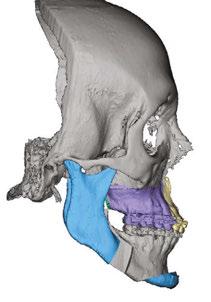

The purposes of the face, in hierarchal order, are 1) breathing, 2) eating, and 3) communicating. The brain prioritizes these purposes by causing all parts of the facial system to work together towards the three goals. When growth is inappropriate, the brain compensates to accomplish the purposes of the face often at the expense of the parts (fascia, muscles, teeth, joints, spine, etc.) These compensations may cause dysfunction, deformation, and destruction (Figures 1-4). Knowing the purposes of the face allows us to define the healthiest place for each individual part of the face. It is that position that minimizes energy expenditure as that part engages and relates with other parts in helping the face to breathe, eat, and communicate.

Figure 1 (left): A photo of a 69-year-old woman with a 2 mm anterior open bite and an excessive interlabial gap of 9 mm. Figure 2 (right): The sagittal slices of the above patient’s mandibular condyles reveal discontinuity of the cortical outline at the fossa and condyle (erosions). The altered condyles are flat along their path of function when she pushes her lower jaw forward to get the lips to touch in speaking, chewing, and breathing through her nose. Image captured using Dolphin® software (www.dolphinimaging.com)

Figure 3 (left): This same 69-year-old has undergone orthognathic surgery (bilateral sagittal split osteotomies and genioplasty) to close her open bite and shorten her anterior face height. This allows her lips to touch at rest and reduces energy usage to breathe, eat, and communicate. Figure 4 (right): The energy reduction at the mandibular condyles allows them to heal as evidenced by the recortication of the bone with the disappearance of the bony erosions. Image captured using Dolphin software (www.dolphinimaging.com)